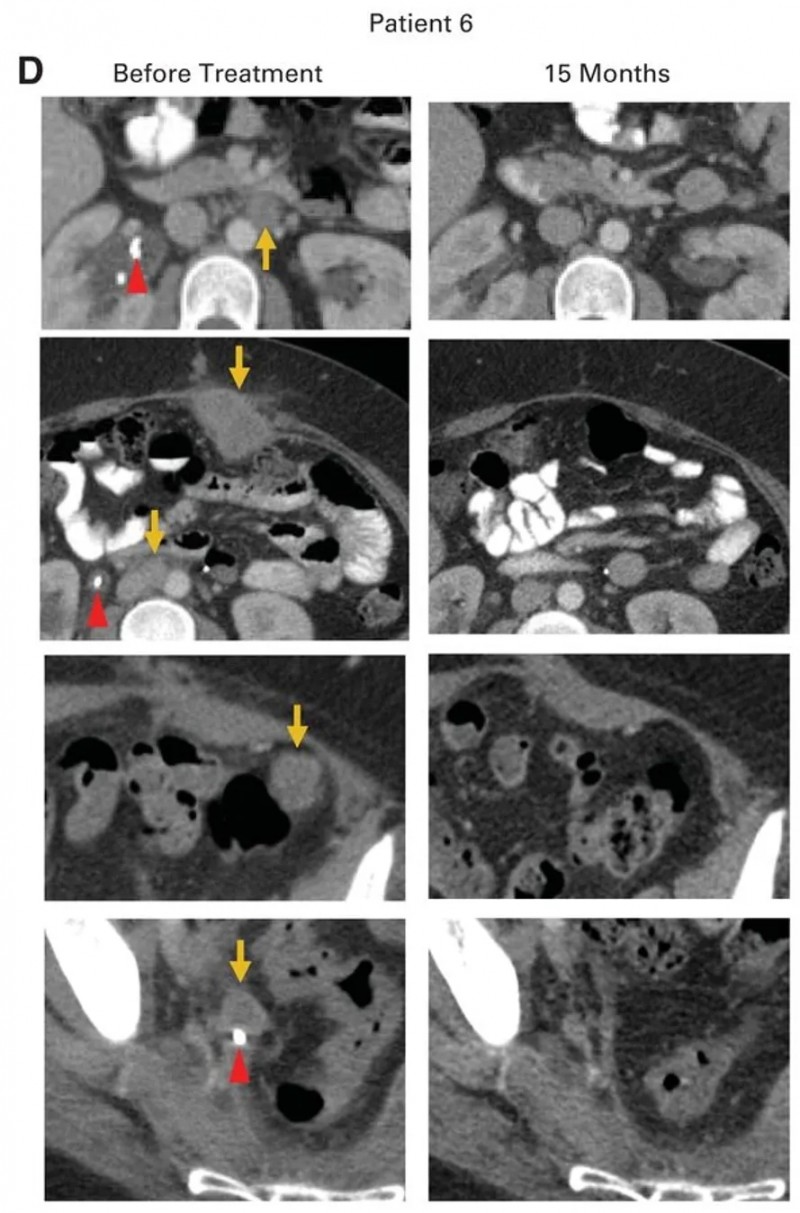

患者6为一例转移性腺癌女性,原发肿瘤对放化疗耐药,经挽救性手术证实腹主动脉旁、髂淋巴结及盆腔其他部位受累;后续癌症进展至腹膜后淋巴结、肝脏表面,伴右侧输尿管肾积水及双侧肺栓塞,需放置输尿管支架并接受抗凝治疗,治疗时腹膜后、腹壁、结肠旁、肝旁及盆腔均有进展性肿瘤。经HPV-TIL治疗后,患者获得完全临床缓解(CR)(详见下图),治疗后15个月无疾病复发迹象,右侧输尿管肿瘤消退后,已成功取出输尿管支架。

▲图源“JCO”,版权归原作者所有,如无意中侵犯了知识产权,请联系我们删除